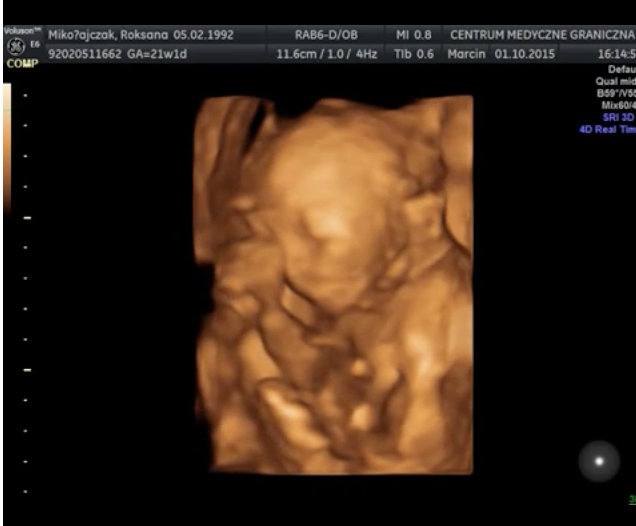

Wyniki badań prenatalnych są bardzo dobre. Obecnie trwa 23 tydzień ciąży, a mała waży 500 gram. Lekarz zalecił mi jednak kontrolę przepływu krwi, ponieważ obecne wyniki mieszczą się w górnej granicy normy 101cm/s. Wykonanie USG nie było wcale takie proste – maleńka Kasia jest bardzo ruchliwa i nie pozwalała się zmierzyć podczas badania. W czasie jego trwania udało się nagrać kilka krótkich filmów i zdjęć, możecie je zobaczyć poniżej. Kolejne badanie prenatalne odbędzie się 10-go grudnia. Termin porodu wyznaczono na 11 lutego i prawdopodobnie odbędzie się za pomocą cesarskiego cięcia.